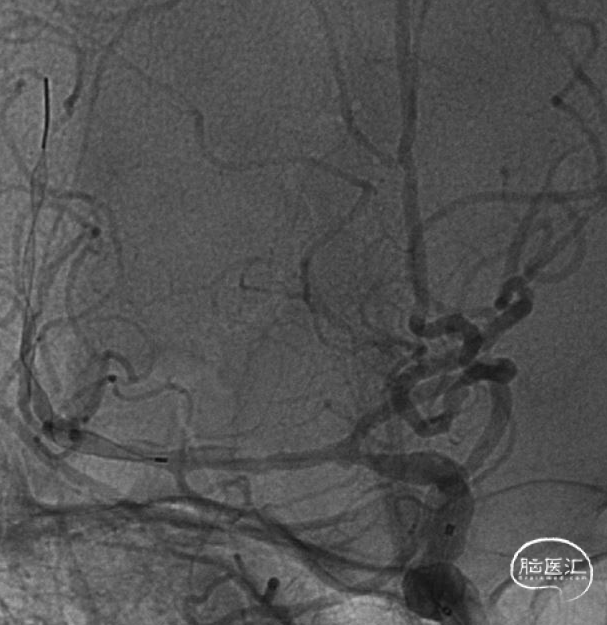

术中DSA

2.0*15mm 球囊扩张

术后造影